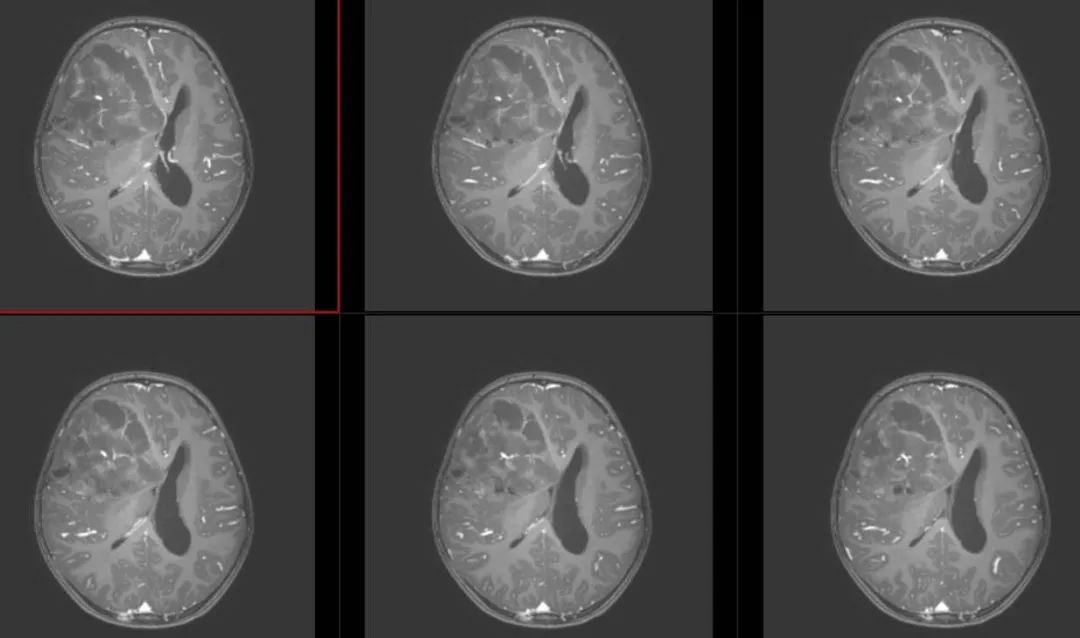

术前影像

术前T1轴位

术前T1冠状位

术前FLAIR

术前T2轴位

术前T2矢状位

术前颅脑MRA、MRV

术前T1冠状位增强

术前T1轴位增强